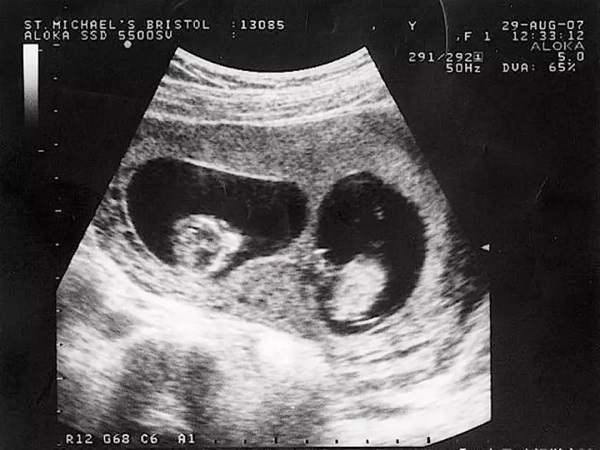

所謂孕囊,其實就是原來的胎盤組織,是被羊膜和血管網包裹的胚胎。孕囊是懷孕的最初形式,一般來說,胎兒還沒有走完旅程,但這個時候,胎心率和胚胎芽就會已經出現了。通過胎心次數,可以判斷出胎兒懷的是單胎還是雙胎。如果有兩個胎心,那麼就是雙胞胎,可能是同性雙胞胎,也可能是龍鳳胎。無論是哪種,孕婦都需要及時去醫院檢查,保證胎兒的健康。一個女人懷上龍鳳胎後,從孕囊上是看不出來的。一般來說,孕囊沒有明顯的特徵,但通過女性懷孕後身體的一些變化,還是可以判斷出女性懷的是雙胞胎。

如果懷孕後,b超顯示兩個孕囊又長又圓,可能是龍鳳胎,但也可能是同性雙胞胎。因為孕囊的大小其實是受胎兒生長髮育的影響,出現長圓形是非常正常的,並不能決定胎兒的性別,所以我建議你不要太相信。需要注意的是,無論是同性雙胞胎還是龍鳳胎,對孕媽媽的健康都是一個很大的挑戰,所以建議孕婦一定要去醫院定期檢查。平時要多注意營養補充和休息,不要太累。當然,也可以適當運動,讓兩個寶寶健康成長。